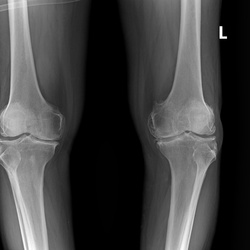

HASIL RONTGEN

3 photos